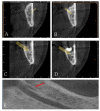

The purpose of this observational study is to evaluate the prevalence and main characteristics of bifid canals within a European adult population, analyzing cone-beam-computed tomography (CBCT). The population study examined 300 subjects. The CBCTs were performed between 2012 and 2019, using PaX-Zenith3D with a standard protocol of acquisition. The parameters analyzed were the presence and lengths of the bifid mandibular canals. The sample included 49% male and 51% female participants. The mean age of the patients was 47.07 ± 17.7 years. Anatomical variants of the mandibular canal were identified in 28.8% of the sides and 50.3% of the patients. In 7.3% of the subjects, the anatomical variants were present bilaterally. The most frequently encountered bifid canal was Type 3 (40.5%), followed by the Type 1 canal (39.3%), the Type 2 canal (14.5%), and the Type 4 canal (5.9%), 40% on the right side and 60% on the left side. The average length of the bifid canals located on the right side of the mandible was 11.96 ± 5.57 mm, compared to 11.38 ± 4.89 mm for those measured on the left side. The bifid mandibular canal is a common anatomical variation of the mandibular canal. It is fundamental to performing an accurate preoperative evaluation using CBCT analysis to avoid and/or reduce intraoperative and postoperative complications.